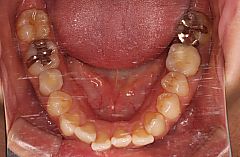

叢生治療例16(唇側矯正、表側矯正、歯科矯正用アンカースクリュー併用、抜歯)

主訴は前歯の凸凹(でこぼこ)です。前歯の凸凹のことを専門用語では叢生(そうせい)といいます。

この症例の場合、歯を並べるために不足しているスペースの量はそれほど多いわけではなく、歯を配列するだけであれば抜歯をせずに治療することも可能ですが、口唇の突出感も認められたため患者様と相談の上、抜歯をして矯正治療を行うことにしました。

この症例でも上下顎両側の第一小臼歯抜歯が候補として考えられますが、上顎左側の第二小臼歯と下顎右側の第二小臼歯にフルクラウン(補綴物)が装着されています。いずれも失活歯(神経が死んでいる歯)でした。

ただ、それを選択すると上下顎ともに左右非対称の抜歯部位となるため治療の難易度が上がり治療期間が長くなります。それで悩んだのですが患者様が歯科衛生士だったこともあり治療期間が長くなることと、左右非対称の力系を補正するために歯科矯正用アンカースクリュー(ミニインプラント)を使用することの了承を得ましたので上顎左側第二小臼歯(5番)、上顎右側第一小臼歯(4番)、下顎左側第一小臼歯(4番)、下顎右側第二小臼歯(5番)抜歯という上下顎左右で非対称な抜歯部位を選択して治療を開始しました。

左右非対称の抜歯部位を選択したことによる固定源歯数の違いを補正するために5本の矯正用アンカースクリューを植立しました。上下顎第一小臼歯を抜歯し、左右対称の力系を組むことができれば本症例ではアンカースクリューは必要ありませんでした。